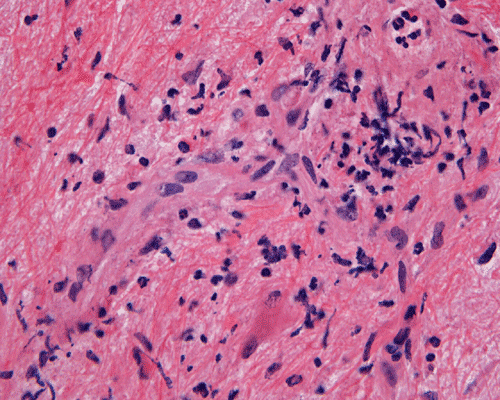

Panel A to E are MR images. Panel F and G are taken from intraoperative cytologic preparation. Panel H to M are taken from frozen section. Panel N and O are from paraffin section. These sections are stained by hematoxylin-eosin stain. Panel P is immunohistochemistry for neurofilament proteins. Panel Q is stained by Luxol fast blue-Periodic acid Schiff (LFB-PAS) stain.

Pathology:

| DIAGNOSIS: Eosinophilic myelitis. |

Pathology of eosinophilic myelitis

Eosinophilic myelitis is featured by lymphocytic infiltration accompanied by a varying intensity of eosinophils. Both the myelin and axons may be damaged. Axonal spheroids can be seen and indicate primary axonal damage rather than secondary damage following demyelination 14, 15. Destruction of axons in the lesion may well explain the relatively poor recovery of this condition. There is increase in eosinophils in CSF in the our under discussion. However, the CSF studies are normal in two previous studies 14, 15.

In addition to eosinophils, predominant CD8 T-lymphocytes infiltration is commonly observed 14. Selective infiltration of CD8 T-lymphocytes into the parenchyma, may suggest the critical pathogenic role of these cells, such as a cytotoxic role rather than a secondary suppressive one. In atopic disorders, acute lesions are characterized by predominant CD4 T-lymphocytes infiltration over CD8 T-lymphocytes infiltration, while CD8 T-lymphocytes predominate in chronic lesions. Therefore, the predominant infiltration of CD8 T-lymphocytes seen in the spinal cord may reflect the chronic nature of the lesions.